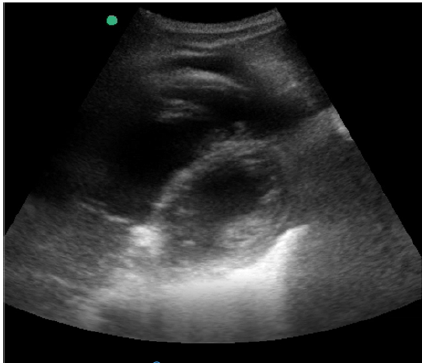

Então, decidiu-se realizar um ecocardiograma beira-leito, cujo resultado é a imagem mostrada a seguir na janela paraesternal eixo curto.

Ainda com o uso da ecocardiografia beira-leito, realizou-se a mensuração da pressão sistólica do ventrículo direito por meio da análise do refluxo tricuspídeo demonstrando o valor de 43,4 mmHg, como apresentado na imagem.

Com base nessas informações e nas imagens, a estimativa da pressão sistólica da artéria pulmonar é de